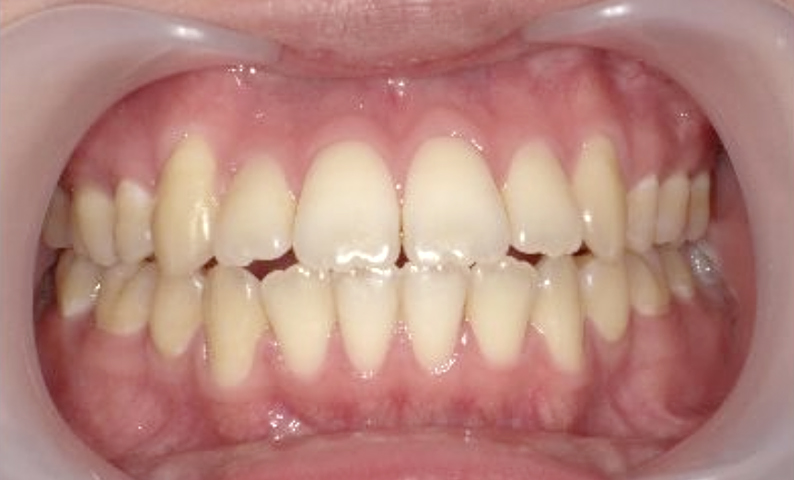

症例_001 上顎だけの部分矯正

治療期間:7ヶ月金額:30万円+税女性出っ歯上の前歯だけ

| Before | After |